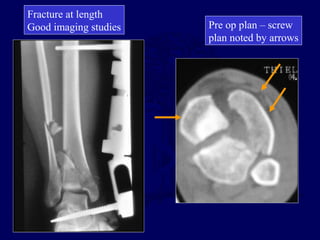

CASE EXAMPLE

28 y.o. female fell 10 ft. Skin at risk, imaging study useless!

Pre op plan – screw

plan noted by arrows

Fracture at length

Good imaging studies

Percutaneous reduction screw fixation according to plan